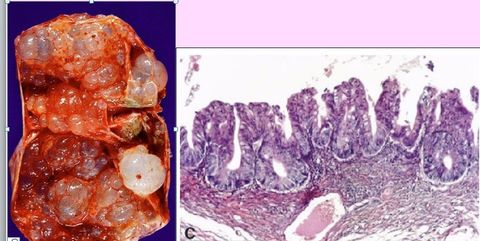

Cistadenocarcinoma seroso.

DIAGNÓSTICO. Qual o marcador tumoral? Cistadenoma seroso benigno. CA 125.

Cistadenoma seroso "borderline"

Cistadenoma mucinoso "borderline"

DIAGNÓSTICO. Qual é o marcador tumoral dessa neoplasia? Cistadenoma mucinoso. CA 19-9.